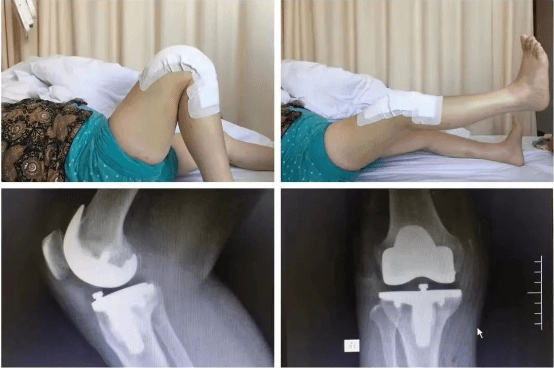

清晨剛上班的骨科門診,來了幾位復診患者,分別是肩袖損傷術后、髕骨脫位術后、膝關節前交叉韌帶斷裂重建術后,膝關節半月板撕裂修復縫合術后的患者。患者見到李鵬主任立即都非常熱情的迎了上來,李主任也耐心的進行了接診,并一一為患者詳細、專業的進行術后康復指導。患者所接受手術的肩、膝關節,活動范圍明顯改善,他還為患者擬定下一階段的康復動作計劃,繼續進行主被動鍛煉,肌力訓練,日常生活行為能力訓練等動作。診療完成后李主任讓患者添加微信,每周拍自己的康復鍛煉視頻發給自己,以便對患者的動作及時進行指導。這一舉動立即讓患者及家屬感受到了作為醫生的良苦用心,他說:“要讓患者挺直腰桿走回家”。這幾位復診患者都有一個共同特點,就是他們受傷后都接受了運動醫學亞專科的關節鏡微創手術,手術后3-5天即可出院,創傷小、恢復快,他們對手術效果非常滿意。

髕骨脫位手術

擅長治療各種骨關節外傷、骨關節疾病。手術方面擅長髖、膝關節置換術、膝關節單髁置換術、脛骨高位截骨術、股骨頸骨折及轉子間骨折等手術。富血小板血漿(PRP)治療骨關節炎。擅長關節鏡下膝關節交叉韌帶重建、半月板損傷縫合、髕骨脫位、肩袖修補,肩峰撞擊征、鈣化性肌腱炎,肱二頭肌長頭腱炎,髖關節盂唇損傷、髖關節撞擊征、踝關節不穩、踝關節韌帶損傷、肩關節不穩、肩周炎、各類關節內骨折、關節脫位的手術治療。